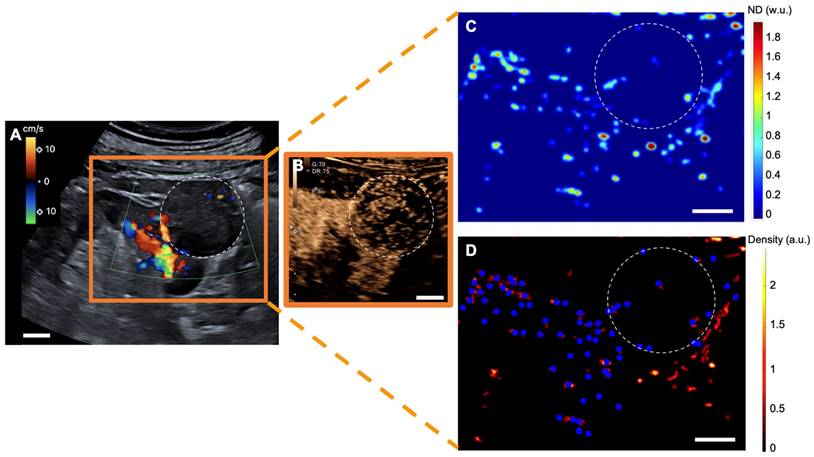

Figure 3

sULM of hypertrophy of the column of Bertin (patient 7). A & B. Superb microvascular imaging Doppler image (A) and CEUS (B) showing an endophytic renal pseudotumor (hypertrophy of column of Bertin) (white-dotted area). C & D show normalized distance metrics. (C) This metric enhances glomerular behavior, highlighting the detected glomeruli in blue points on the density map. (D) Note the presence of glomerular paths in the renal cortex and the pseudotumor. (The traces projected on the grid are displayed in red on the image. The colorbar corresponds to the count of the number of bubbles per pixel. Scale bars indicate 10 mm. ND= normalized distance; w.u.= without units; a.u. = arbitrary units.